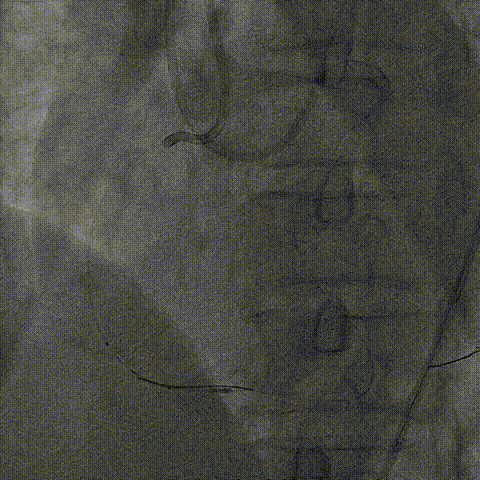

血管内超声:

导丝远端位于血管真腔,闭塞段部分内膜下走行,可见闭塞段钙化,符合术前评估结果。

支架植入:

根据血管内超声结果,在Telescope™支撑下序贯植入3.0mm、3.5mm、4.0mm支架3枚,4.0mm直径支架通过Telescope™延长管顺畅,无连接部剐蹭情况。

6F Telescope 支撑下序贯植入Ø3.0 3.5 4.0mm支架,通过性优异